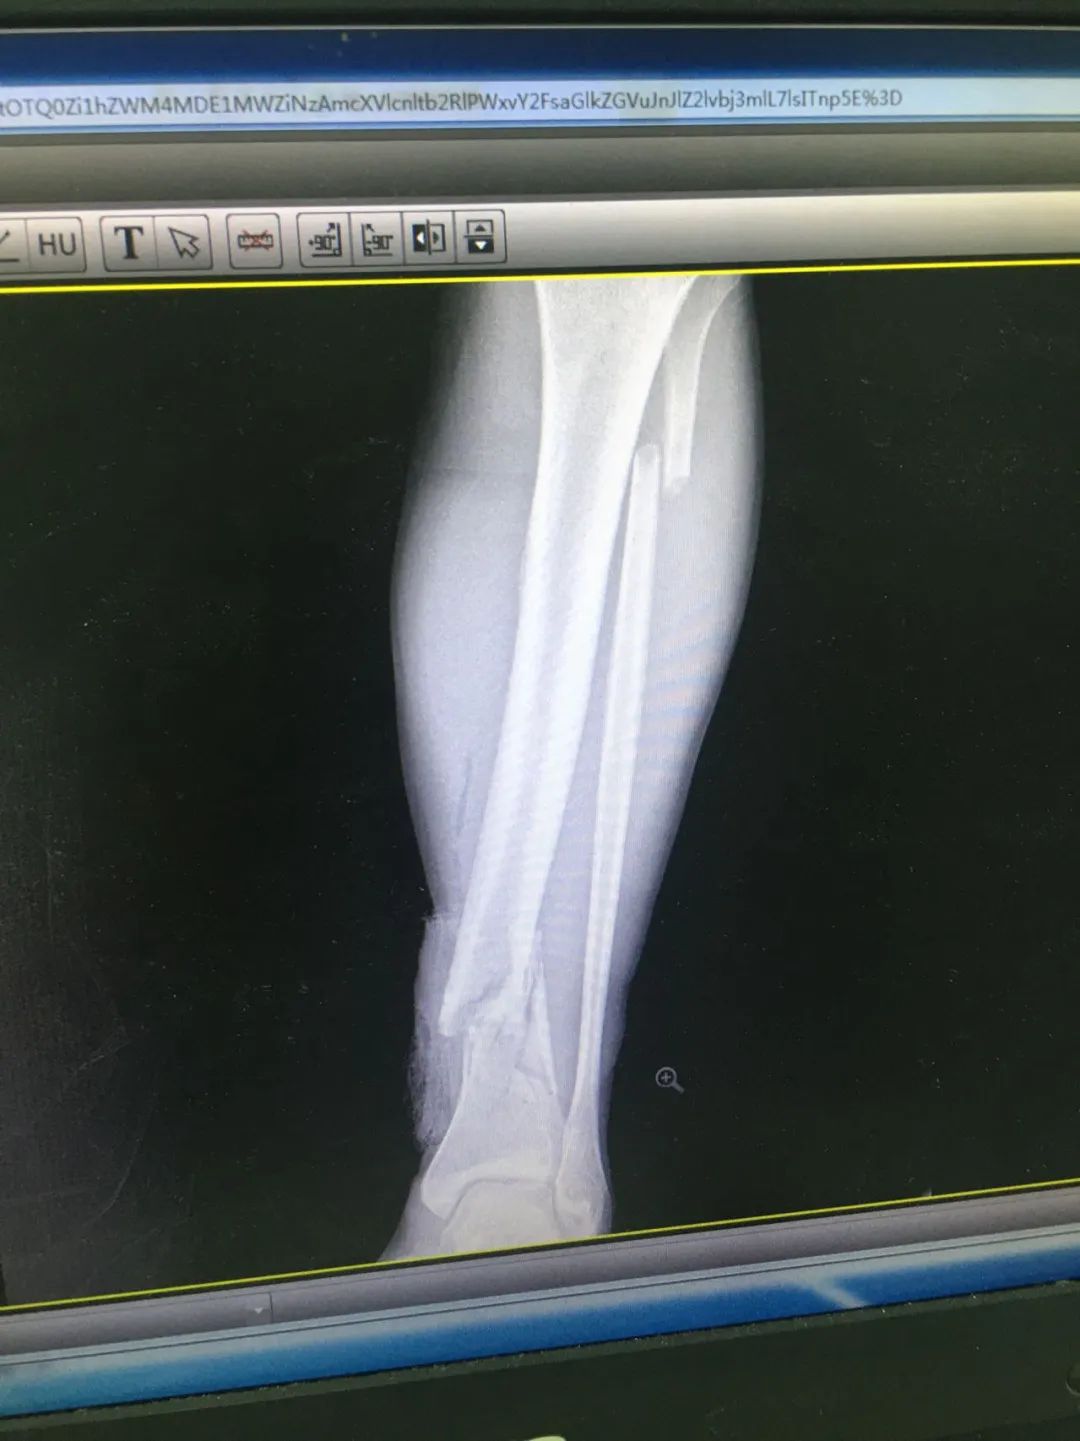

入院時,劉先生已失血性休克。急診科為劉先生安排X線及CT攝片檢查,顯示左股骨干、左腓骨上端骨折,左脛骨遠端粉碎性骨折,頭皮及全身多處皮膚軟組織挫裂傷,隨后收治于骨科。

第1次手術10天后,骨科為劉先生安排了第2次手術,歷經(jīng)3個小時,成功完成左股骨干骨折及左脛骨遠端骨折閉合復位內(nèi)固定術,植入兩根30cm×10mm、34cm×10mm髓內(nèi)釘。

術后一周,患者手術切口愈合良好,左下肢皮膚感覺及肌力正常,左足末梢循環(huán)恢復,復查X片顯示骨折復位標準,內(nèi)固定物位置良好。